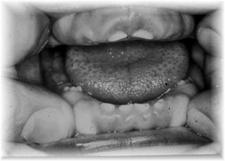

Gingivite

sângerare la periaj/sondare

gingie de culoare rosie, tumefiata, neteda, lucioasa, sensibila la palpare

halena

pungi parodontale false

ANUG

elefantiazis gingival